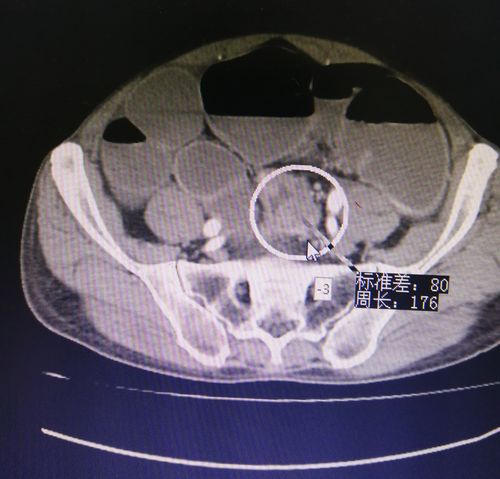

肠梗阻CT